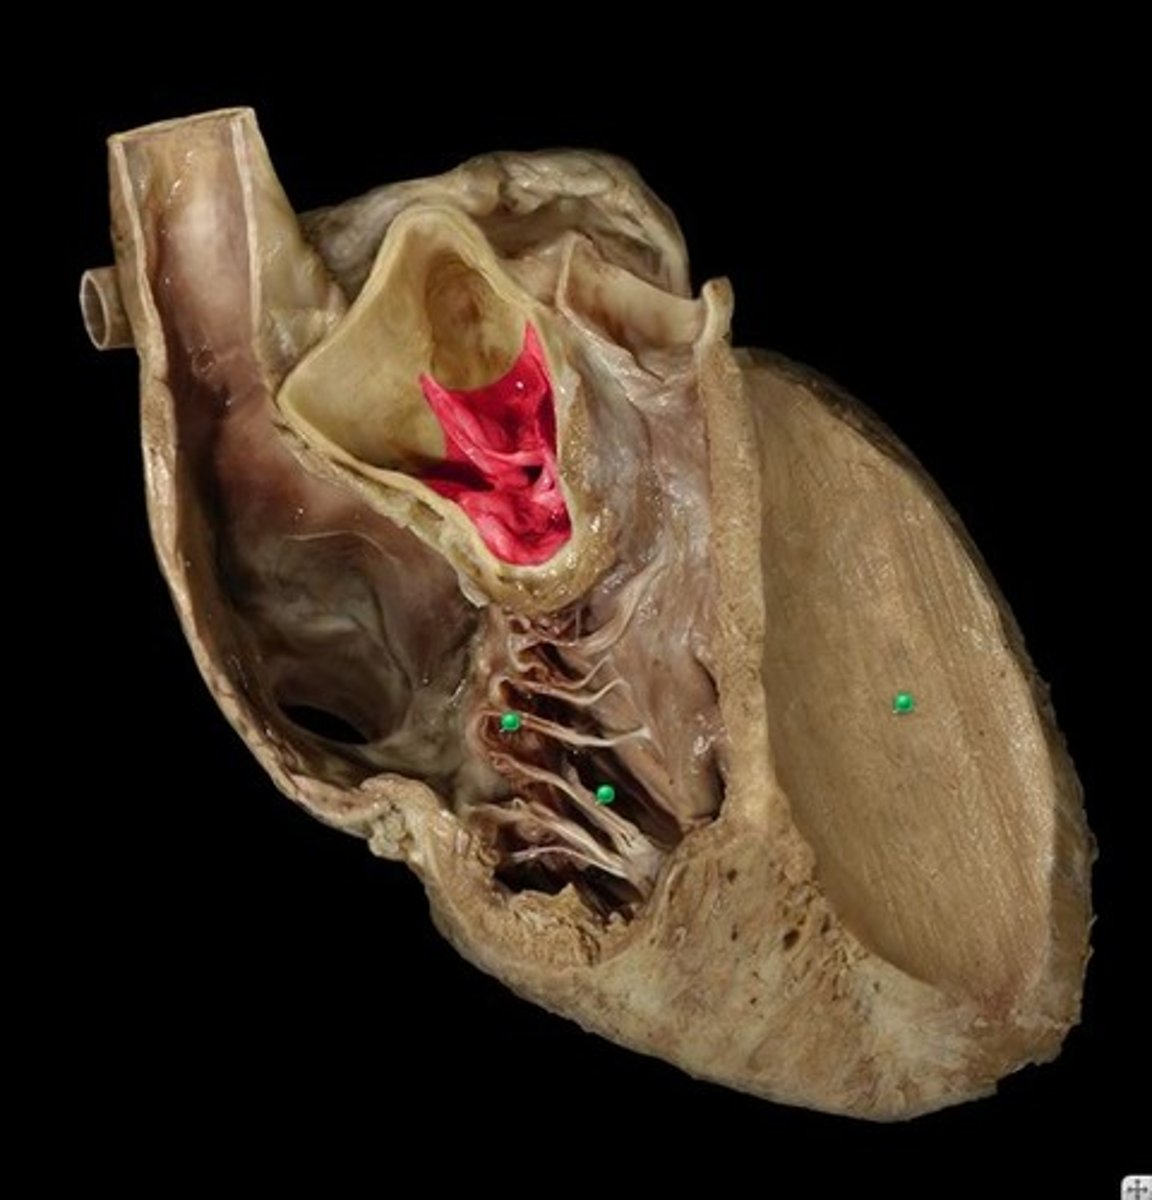

Interatrial septum

collective Structure; pinch between left and right atrium

Fossa ovalis

depression

in R atrium, pinto bean buried in R atrium

Pectinate muscle

st

stretch jeans on inside of right atrium

webbing on wall of R atrium

Sinus venarum

surface; on inside of right atrium, smooth part, by fossa ovalis

Right atrioventricular orifice

Space, stick probe from atrium to ventricle to open doorway

tricuspid valve

Structure; closed door, three flaps

mitral valve (bicuspid valve)

Structure; door in between LA and LV

2 flapped valve

aortic vestibule

Narrowing; open heart in half, narrowing below the flaps

Aortic valve

Entire structure; all 3 of the drapes above the narrowing in LV

semilunar cusps of the aortic valve

Component; only 1 of the 3 drapes